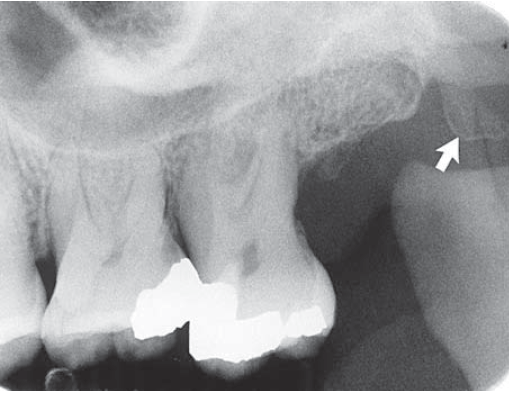

28. What is showing by arrow?

29. What is shown by the arrow?

30. What is shown by arrow C?